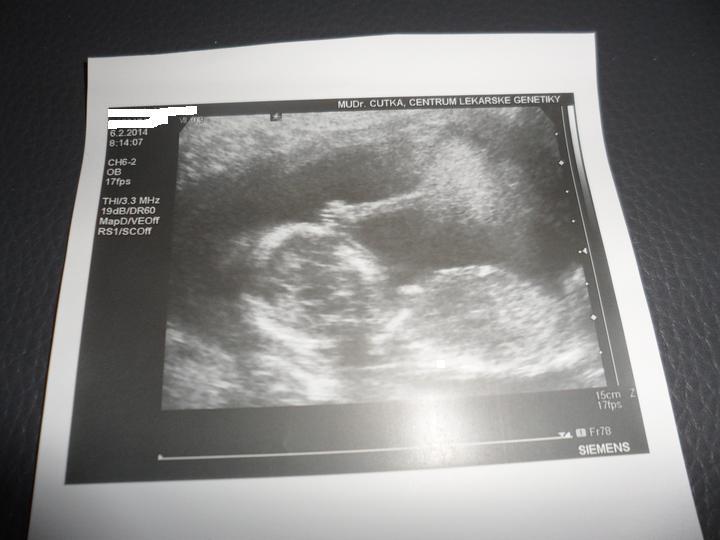

v pátek nám přišly výsledky z plodové vody a vše je v pořádku, čekáme zdravé miminko 🙂 jsme moc šťastní !!

Holky nemáte zkušenosti s Centrum lékařské genetiky v Českých Budějovicích? Jsou tam v pohodě?